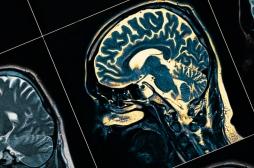

LES MALADIES

J'AI MAL